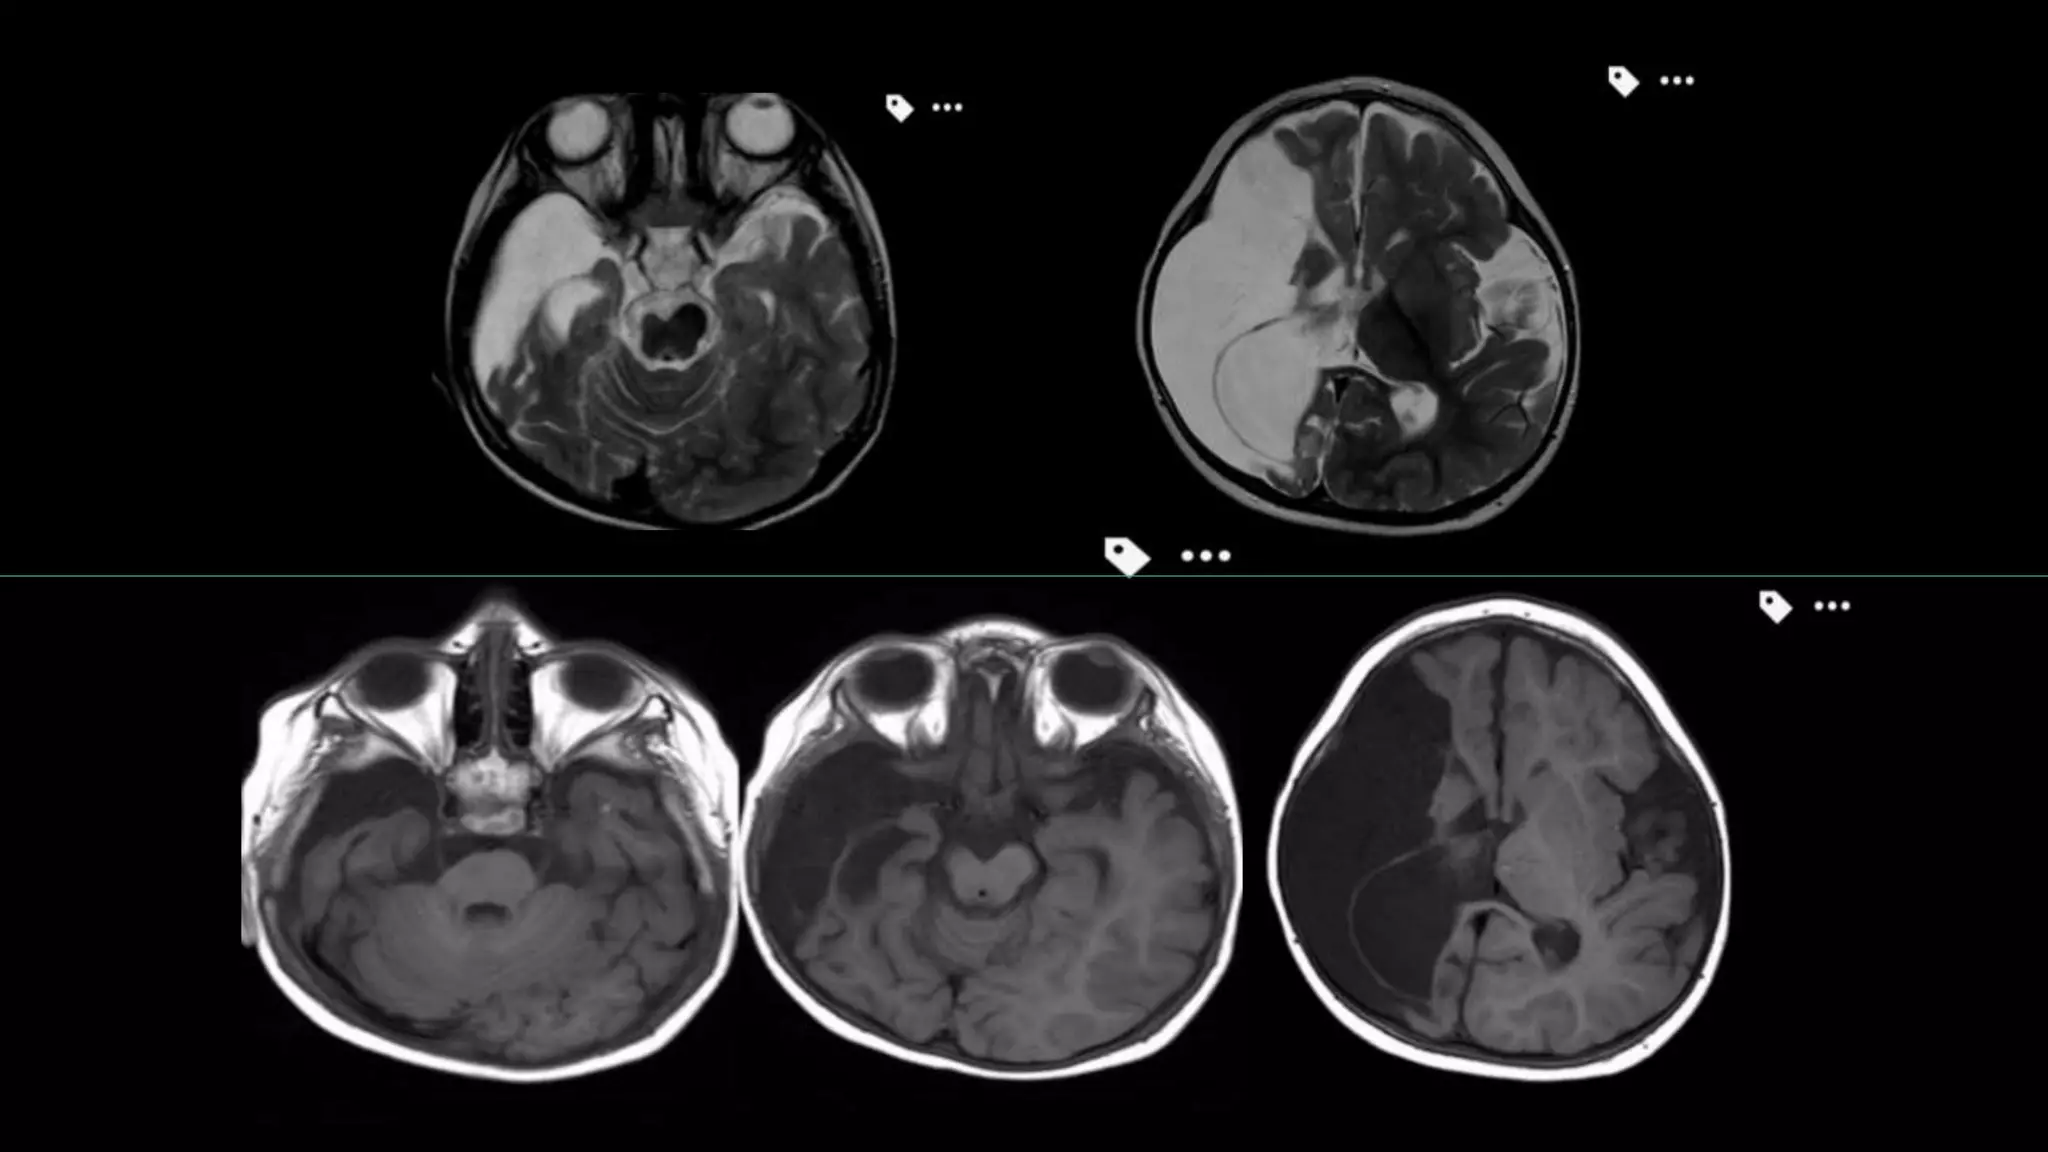

• #123 C/o 75 y old men showing T1 hypointense and T2 hyperintense foci in mid pons

• #124 Showing signal suppression on FLAIR image with no enhancement on post contrast scan s/o chroniclacunar infarct. Also there are T2/FLAIR hyperintensities in subcortical and periventricular white matter b/l s/o ischemic demylination and glioenchephalomalcic changes in right parietal refgion

• #125 This is the another c/o CHRONIC LACUNAR infarct in right basal ganglia appearing hypointense on T1/ hyper on T2 with signal suppression on FLAIR